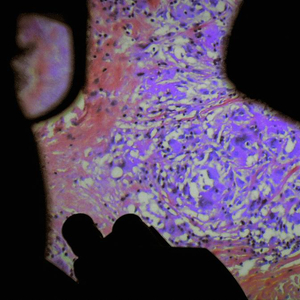

韦雷娜·帕拉维尔(Véréna Paravel, b.1971)和吕西安·卡斯坦因-泰勒(Lucien Castaing-Taylor, b.1966)的《人体的构造》(De Humani Corporis Fabrica, 2022)延续了他们以往“身体-景观-感官”的脉络,成为一部由医学影像构成的电影——内窥镜(Endoscopy)影像,肿瘤切片检查(Pathological Examination),X光放射前列腺电切术(TURP),白内障手术(Cataract Surgery),剖腹产手术(Caesarean Operation),脊柱融合术(Scoliosis Surgery)……当代医学成像技术记录下人们能日常感受却全然陌生的身体器官内部,这些怪诞而抽象的景观构成了影片的主体部分,而游走在医院空间的手持摄影机则试图探讨身体痛苦的精神转化过程,身体如何被矫正和驯服,病痛对医患的分配体制以及生命权力的转移。图像的声音空间被医疗机械运转的声音、病人的呼吸和呻吟以及医生的对话、指令和抱怨填充,也将强烈的图像本身在一定程度上消弭,并延伸至同样充斥着身体的社会空间——正如导演所阐述的,“医院装满人的身体,社会亦然”。这种“人体-医院-社会”的线索也在暗示一种生命状态逐渐从形式(form)分离并赤裸(bare)的过程。

苏珊·桑塔格(Susan Sontag, 1933-2004)在《关于他人之痛》开篇部分谈及伍尔夫(Virginia Woolf, 1882-1941)所说的“每次我们观看(战争图像),我们都能感同身受”时,指出其中主语“我们(we)”所指代的含糊性➀,她认为“痛苦”是无法移情的,或者至少痛感的移情并不是可以批量式的,因此自然也就不存在一个统一的受众——“我们”。克洛伊·加利贝特-莱奈 (Chloé Galibert-Laîné)在她的视频论文《观看他人之痛》(Watching The Pain of Others, 2018)中分析了潘尼·莱恩(Penny Lane)的影片《他人之痛》(The Pain of Others, 2018),并尝试揭示出这种身体痛苦转译过程中的由于媒介操控而产生的心理线索的失准和断裂。在影片《人体的构造》中,观众可以看到疗养院中坐在房间中不时叫喊的痛苦的老妇人,她间歇性地张开嘴巴释放苦楚的呻吟,也一并排解释放痛苦,而观众却无法感受她的痛苦;而影片的白内障手术中,镜头瞄准伸向瞳孔的尖锐手术刀具,尽管被手术的患者已经被麻醉,感受不到太多痛苦,但观众席上却唏嘘一片,纷纷离席。“他人之痛”的概念触及到的是痛苦的展演(performativity)。当镜头只用超特写镜头展示手术中人的瞳孔和手术刀,大部分观众可以接受这样的镜头,当镜头稍微拉开,展示出眼睑和抽动的眼眶,观众则更多的意识到这是人的器官,进而对痛苦表现出更多的负面反应。

如果说痛苦的移情是可被构建的,那么什么才是痛苦的本真(authenticity)?医学机械穿透幽深的人体内部,直接将信息传输到手术室,是否足以展示痛苦?正如《人体的构造》影片所展示的,这一接近过程也伴随着医生的指令和操作,痛苦的流淌伴随着图像的流淌,这一流淌过程除了导演展现给影院内的观众,它们的首要制作者和观众仍然是医院的医生,而影片通篇都在展示这种痛苦移情的不可能,甚至是这种不可能作为医疗行为的前提——一种“不够人道”的人道主义。在这个前提之下,《人体的构造》似乎很容易使观众误解为是在展示“医生-患者”间的权力关系;然而导演始终在试图将病人和医生之间的不平等消弭,并企图说明医生和病人同样都是“神圣人”,都在非常态下被剥夺着权力。比如影片开篇就有护工在画外音中疲惫地倾诉着每天医院接到的电话太多,而大部分只是病人需要心理陪伴;大部分医生都在抱怨假期太少,工作压力太大;男科医生抱怨自己实施阴茎手术太多,已经严重影响到自己的性功能……影片尝试将两个群体统一化,使医院拥有一个“绷紧并和谐”的内核,这种将两者共同体化的处理方式使得影片对医院外部的权力结构的暗示作用变得更加强烈。如果说画外音仍不能将医生-患者的权力结构打破,《人体的构造》以医生的派对狂欢为结尾,醉酒后随着“新秩序”(New Order)音乐舞动的躯体、桌面足球游戏台的小人、淫秽的墙上涂鸦、被篡改的《最后的晚餐》,仍旧是低照度下慢门近距离摄影,图像的拖拽残影将人的肢体动作放大并模糊;以上种种图像操作强化了一种“污秽化”(profanation)行为,向一种阿甘本所提出的“嬉戏”(play)的解决策略倾斜。遗憾的是我们显然看不到患者的更多行为,因为影片中出现的患者大多处于麻醉的无意识状态。